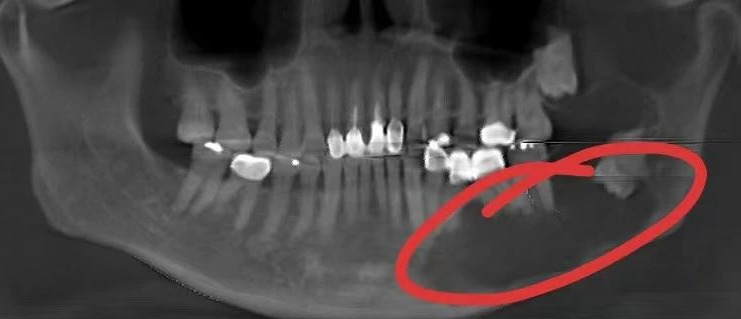

如果是完全阻生的牙齿,还可能在骨内形成囊肿,造成下颌骨吸收,形态破坏。